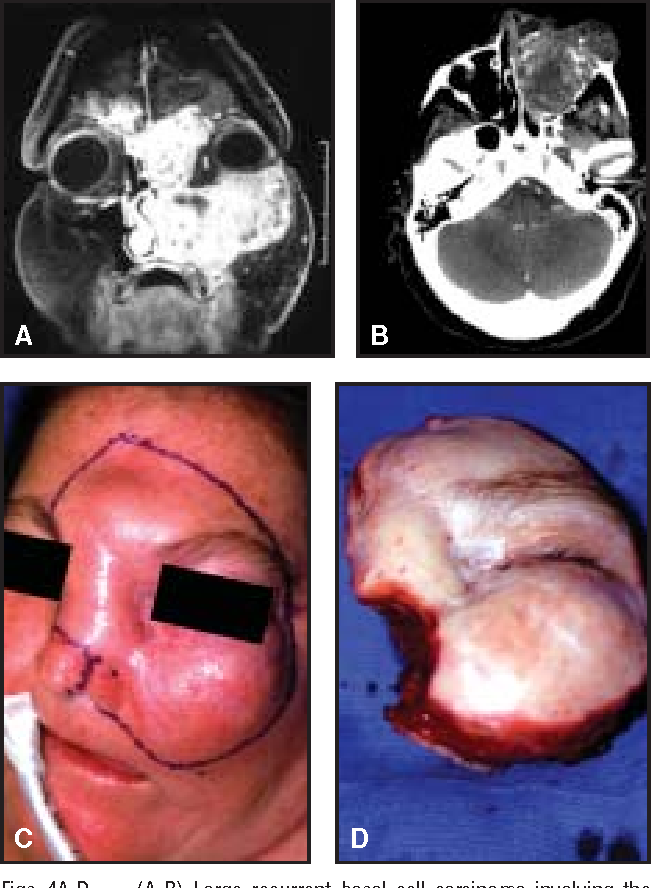

If done nasally, you are at risk of maxillary tumors.

Though the risk is low, if you don't want to look like this deformed jeet, either pin it or opt out

If done nasally, you are at risk of maxillary tumors.

Though the risk is low, if you don't want to look like this deformed jeet, either pin it or opt out